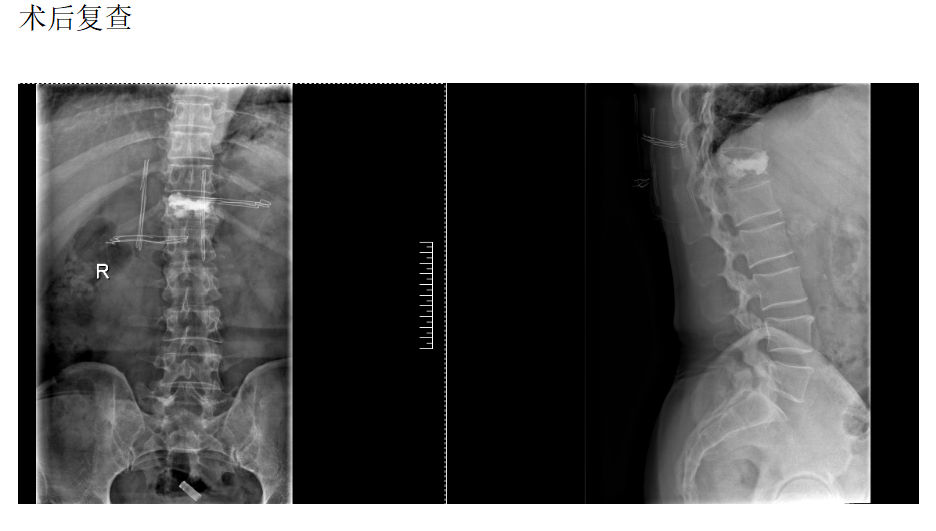

脊柱外科组(骨折、畸形、复杂融合固定)

脊柱骨折病历

现病史:半月前坐凳子时不慎摔倒出现腰部疼痛、酸困,无下肢疼痛麻木不适,弯腰活动受限,行走及站立时疼痛加重,平卧休息稍减轻,无发热,无下肢局部红肿,未治疗,上述症状持续加重,为求诊治,现来我院,遂以“T12椎体骨质疏松性压缩骨折”为诊断收住我科。发病以来,饮食正常,睡眠一般,体力正常,大小便正常。